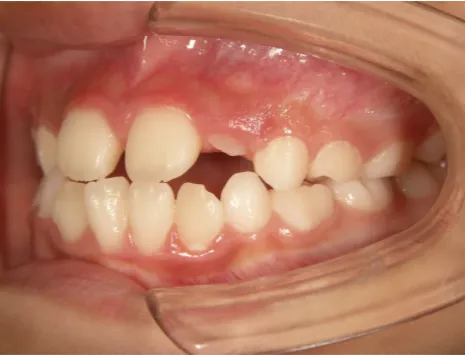

治療中➁小3:9y8m QH、BH、前歯並び替え終了

モノブロック装置(筋機能的咬合誘導装置)スタート